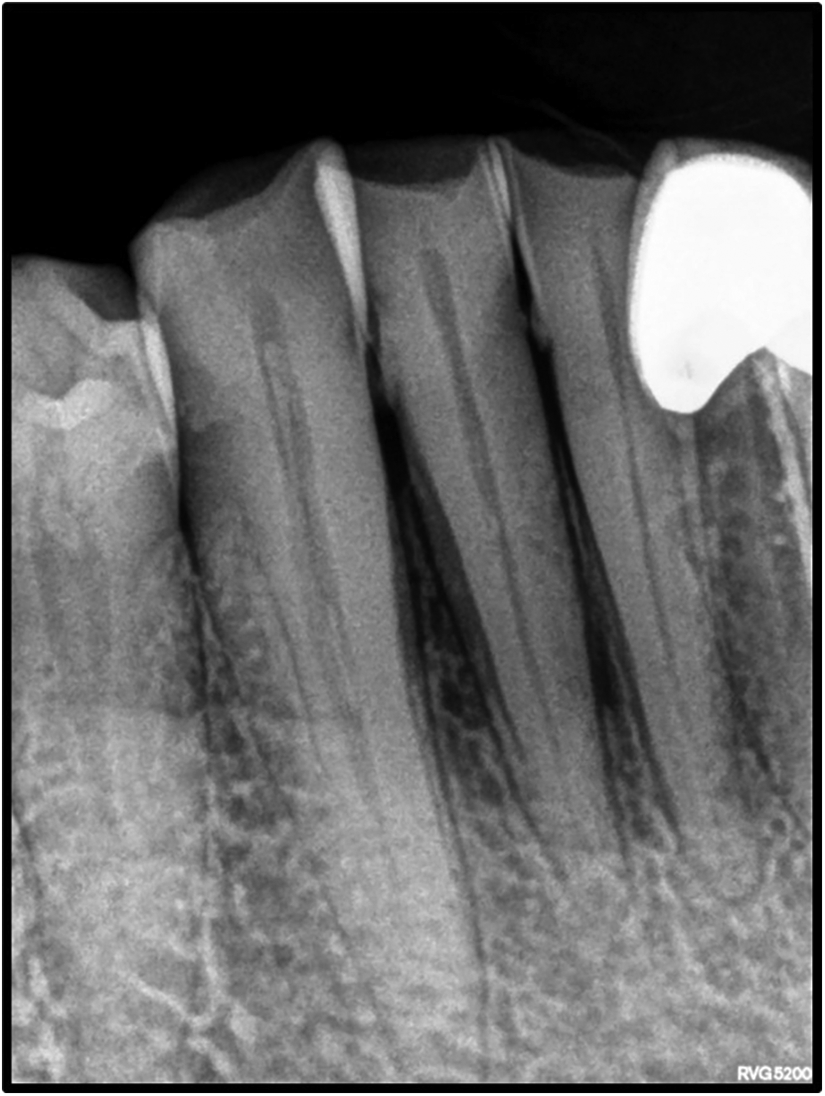

On intraoral examination, there was a gingival lesion on the labial aspects of 41, 42, and 43, extending from the mesial aspect of 41 to the distal aspect of 43. The lesion involved marginal, interdental, and attached gingiva. The gingival lesion appeared to be erythematous, and the surface was irregular with erosions. The margins of the lesion were well-defined with raised edges. It was soft in consistency and tender on palpation. On periodontal examination, there was the presence of bleeding upon probing, with no exudation. There was a moderate deposition of calculi. There was an absence of mobility i.r.t 41, 42, and 43. There was no tenderness on lateral and vertical percussions on teeth i.r.t 41, 42, and 43. The rest of the oral mucosa had no significant findings. On extraoral palpation, submandibular lymph nodes on the right side were palpable, firm, non-tender, and mobile. An intraoral periapical radiograph (Figure 2) was taken and revealed mild horizontal interdental bone loss in the regions 42 and 43, which suggested chronic periodontitis.

FIGURE 2

www.frontiersin.org

Figure 2. Intraoral periapical radiograph showing 41, 42, and 43 with mild horizontal bone loss.

The most common sites of OSCC are the tongue and the floor of the mouth, followed by the soft palate, gingiva, and buccal mucosa. OSCC of the gingiva is normally painless and its incidence ranges from 2 to 27% (23, 24). Gender predilection is ambiguous with respect to GSCC, with some studies reporting female predilection (25) and others reporting male predilection (26). Mandibular involvement is usually more common than the maxilla. Additionally, GCSS is generally associated with non-traditional risk factors and is found in non-smokers and non-drinkers (1, 27). It is an insidious disease that is present without the typical clinical features attributable to malignancy and is frequently misdiagnosed as a periodontal inflammatory lesion. In such cases, presentations that could indicate malignancy include erythema with non-healing ulcers and red lesions with a granular surface texture that bleed profusely (1). It usually begins with the keratinized mucosa, quickly progressing to involve the underlying bone structure with ensuing tooth mobility (28). As the thickness of the attached gingiva is 2–3 mm, gingival carcinomas tend to involve the bone at early stages and can spread easily (29, 30). Dental extractions are usually carried out in cases that are misdiagnosed as periodontitis. Dental extractions lead to bone invasion and further spread, worsening the prognosis of the patient (31). It is essential to evaluate bony involvement in GSCC cases. Radiographic features that help distinguish malignant involvement as opposed to bone loss related to periodontitis include irregular bone loss with an associated moth-eaten appearance, non-uniform widening of the PDL space, and the absence of sclerosis of trabeculae that is associated with bone loss secondary to periodontitis. Thus, clinical and radiographic features should be carefully examined to diagnose gingival carcinoma at an early stage. This case had an insidious clinical presentation of redness of the gingiva that could be mistaken for a benign lesion. Additionally, there was an absence of typical malignant changes on the radiograph, with bone loss and accompanying sclerosis indicating chronic periodontitis. Furthermore, the lesion was associated with severe pain, which is unusual for a benign lesion. Although early stages of OSCC may be asymptomatic, pain is often an indicator of the transition of a potentially malignant lesion into a cancerous lesion and often the first presenting symptom in oral cancers. In this case, the severe pain and a lack of response of the lesion to local therapy was the main reason for suspicion and warranted further investigation (32, 33). A similar case of GSCC was reported by Brooks et al., in which ulcerations confined to the palatal marginal gingiva confined to the maxillary molars associated with profuse bleeding were observed.